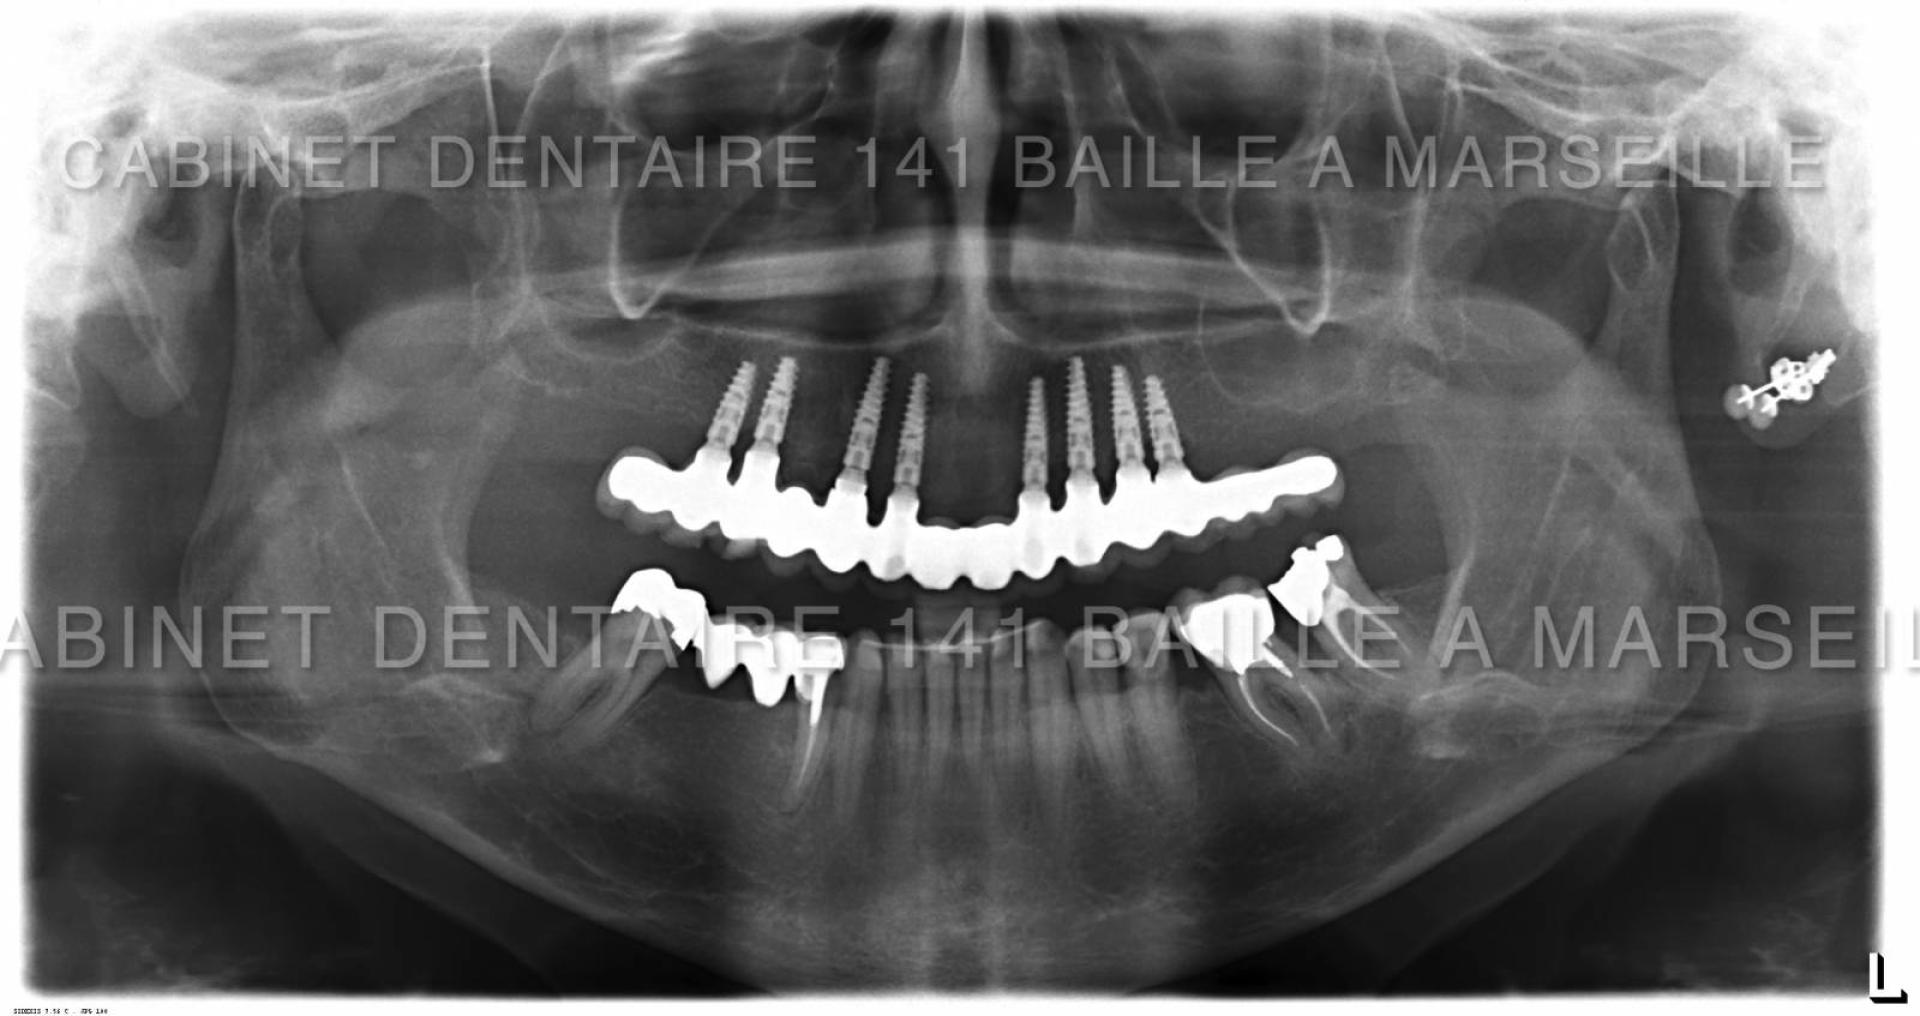

Nous sommes en mesure d'assurer la prise en charge de vos patients dans notre structure qui englobe la phase chirurgicale traitée naturellement en bloc opératoire stérile ,et sytème de traçabilité chirugicale aux normes hospitalières (Cycles prions à fractionnement de vide) ,pour tous les cas complexes intégrant implantations totales avec mise en charge immédiate.

Notre laboratoire intégré nous délivrera une prothèse immédiate qui permettra à votre patient de na pas avoir de gêne au niveau de sa vie sociale.

En général nous commençons à opérer le matin vers 9 h et la patient rentre chez lui vers 13h équipé d'une prothèse immédiate implanto- portée.